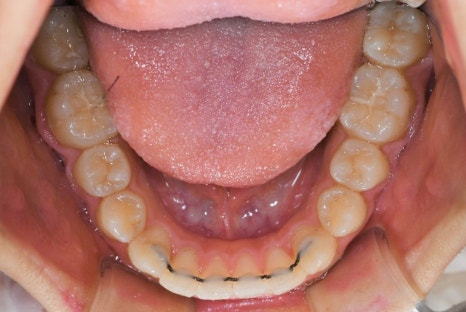

이가 가지런히 펴진 것을 알 수 있습니다.

교정 치료를 마무리 한 후에는

유지장치를 붙이게 됩니다.

이가 돌아가지 않고

유지할 수 있도록 하는 것입니다

만일, 장치가 떨어졌다면

치료받은 치과에 방문하셔서 다시 붙여주셔야 됩니다